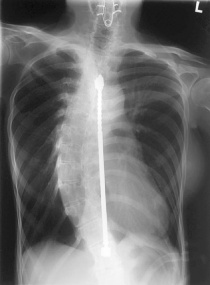

Сколиозата е деформация на гръбначния стълб и води неизбежно до деформиране на ребрата и целия гръден кош, променя формата и нормалното взаимоотношение на гръдния кош и гръдните органи, води до твърде тежки функционални нарушения. Сколиотичната болест не е местно изкривяване на гръбначния стълб, а тежко общо заболяване, което въвлича в патологичния процес всички най-важни и значими системи и органи на човешкия организъм.